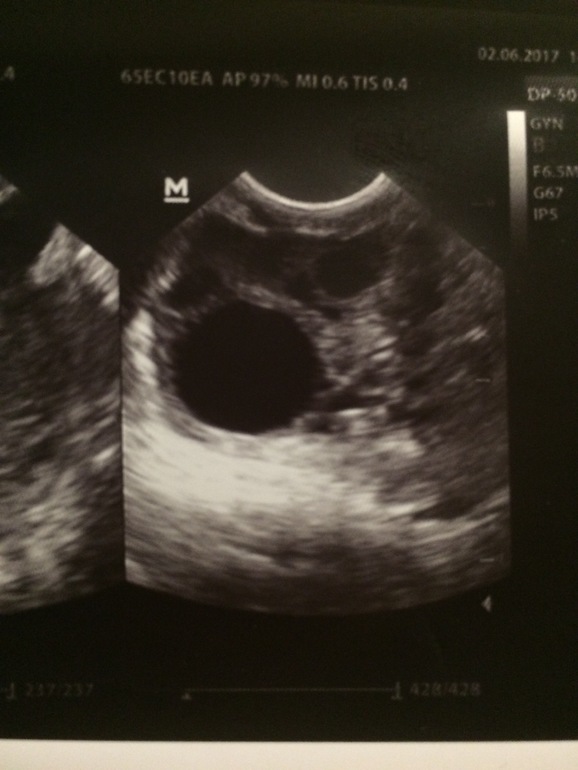

Девочки, кто разбирается, подскажите, что на фото? Фоликул или жёлтое тело?

знаете вроде ДФ,.. но у меня например киста ЖТ выглядела ровно так же... так что всё что тут пишут не гарантия ничего... там надо смотреть кровоток еще чтоб понять что это

Врач сказала: фоликул, либо жт 16 мм. Она сама точно не знает. Но есть жидкость. Поэтому она вначале сказала, что овуляция была. Но все же не написала, что это жт. На момент осмотра был 15 дц. По бт на 15 дц не было еще О. Кровоток на том аппарате УЗИ, я думаю, нельзя было посмотреть.

График БТ, жидкость за маткой и внешний вид.

Это снимок на 15 дц. По бт вроде не было тогда овуляции.

100% дф, так как круглый и черный

жт обычно серого цвета

возможно он овулирует, вот и жидкость, а может их было два

но это точно не жт.

16 мм. маловат для овуляции. вот насчет двух не знаю. до этого не смотрела.

единственное волнуюсь чтоб никакого воспаления не было. пишут что изза него может быть жидкость.

ДФ. Жт обычно неправильной формы и серое